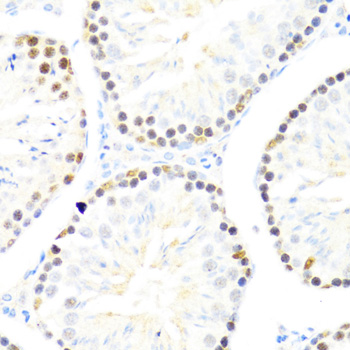

Immunohistochemistry of paraffin-embedded mouse testis using DDX50 at dilution of 1:100 (40x lens).